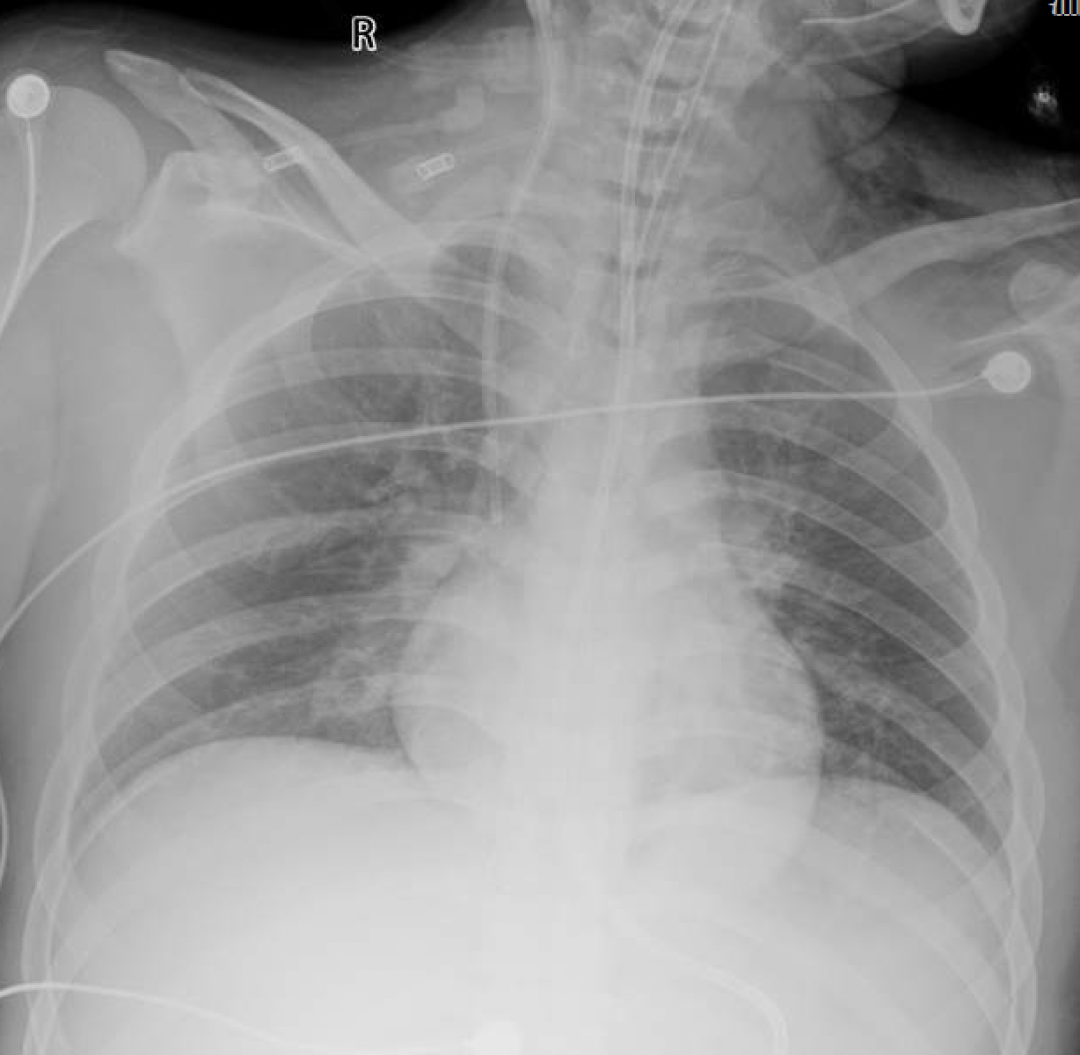

气管镜检查

患者入院后24小时内氧合急剧恶化,呼吸频率38次/分,呼吸窘迫明显。10月26日行气管插管,插管后气管镜下见两侧支气管充血,有黄白色分泌物(图4)

图片

图4  气管镜检查